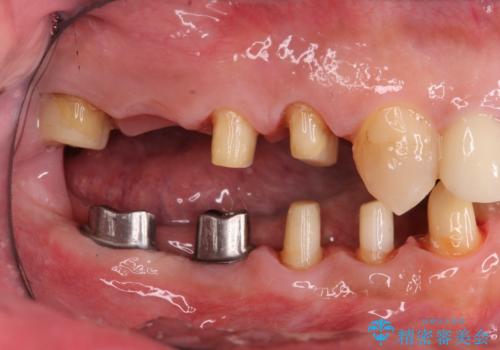

- 銀歯だらけの口腔内を全てきっちり治療したい、と希望され来院されました。

検査の結果、残すことの難しい歯をインプラントに置き換え、残すことのできる歯は虫歯の徹底的な除去後にセラミック治療を行っていくこととしました。

- 125万円(インプラント×2・チタンカスタムアバットメント×2・ジルコニアクラウン×4・仮歯×4)費用は治療当時の料金となります